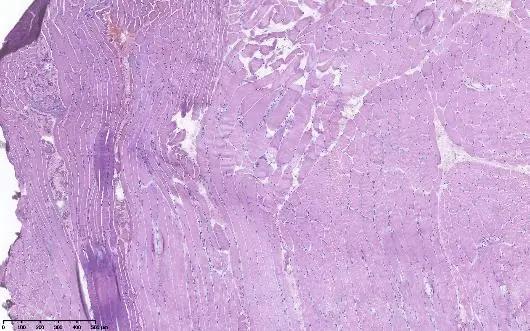

左侧腓肠肌活检:高倍镜下:显示肌束膜水肿伴炎细胞浸润;NADH酶组织染色,显示虫噬现象

王誉萱博士(病理科)点评:

低倍镜下可见肌纤维较一致,无淋巴组织浸润、纤维组织增生;但高倍镜下可见少量肌束膜水肿伴炎细胞浸润,肌纤维坏死萎缩,个别肌纤维束内镶边空泡改变,但对于诊断无特异性价值。NADH酶组织染色可见虫噬现象,SDH和COX染色未见线粒体肌病特征性改变。活检组织大体可见病变轻微,未见典型炎性肌病、代谢性肌病、线粒体肌病改变,不排除遗传性肌病或结缔组织病相关较轻的肌肉病变。